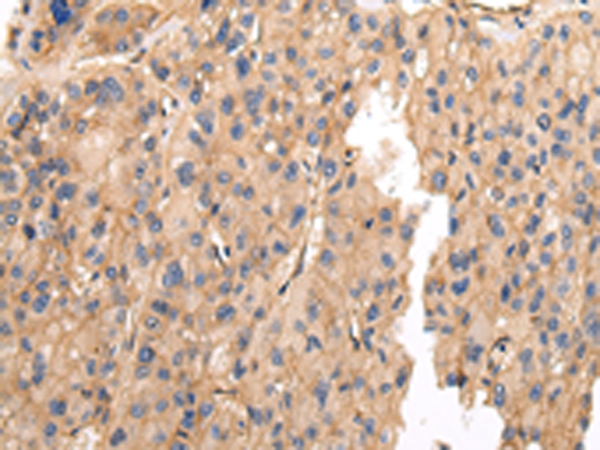

IHC positive control: |

Human prostate cancer and Human thyroid cancer |

IHC Recommend dilution: |

25-100 |